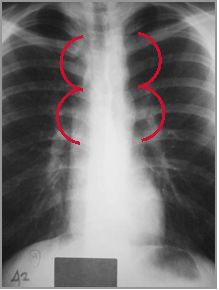

Reverse 3 sign

on barium filled

esophagus

“Figure 3 sign”

caused by

coarctation

Coarctation of the Aorta